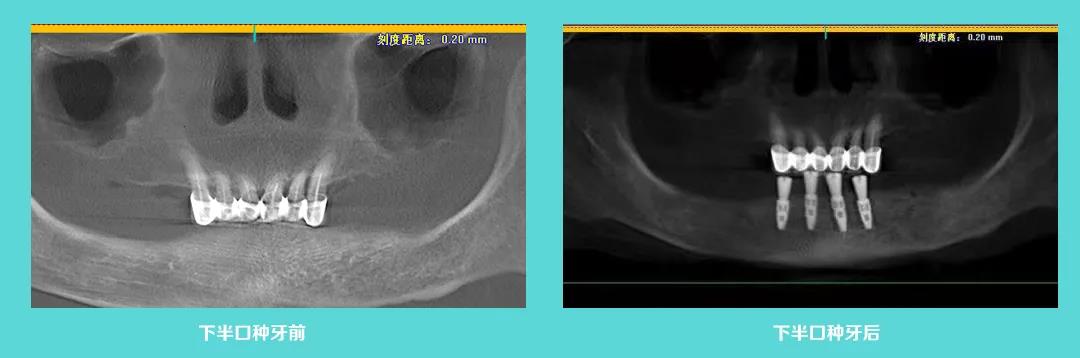

上图为数字化导板种植牙前后对比图,顾客原本骨头偏低,周围神经密集,利用数字化导板科学种牙,精准植入,避开神经,麦芽团队成功为一位七十多岁的老人种上新牙。麦芽数字化精准种牙,效果可预见,数字更精准,体验更舒服,稳定更持久。